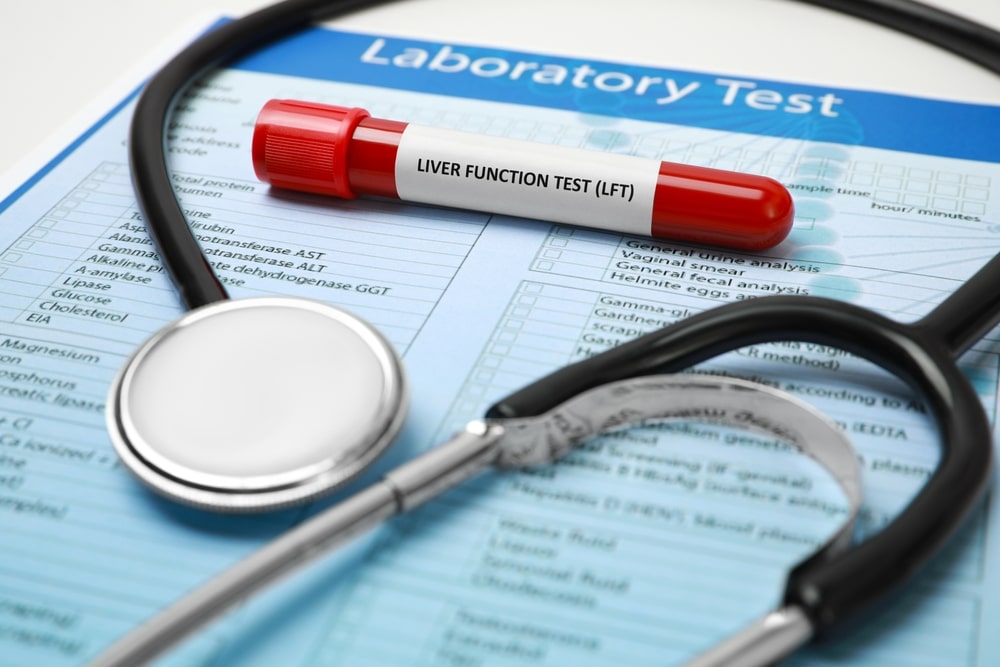

۷. تستهای عملکرد کبد و پانکراس (LFTs & Amylase)

اگرچه این اندامها مستقیماً “لوله” گوارشی نیستند، اما بدون آنزیمهای آنها، هضم در معده و روده مختل میشود.

- لیست موارد مورد بررسی:

- سطح آنزیمهای کبد (ALT, AST).

- سطح بیلیروبین (برای تشخیص زردی و انسداد مجاری صفراوی).

- آنزیمهای پانکراس (آمیلاز و لیپاز) برای تشخیص پانکراتیت.

- شرح آزمایش: این یک آزمایش خون ساده است که هماهنگی اندامهای جانبی با معده و روده را نشان میدهد. بسیاری از دردهای ناحیه فوقانی شکم که بیمار تصور میکند مربوط به معده است، در واقع ناشی از سنگ کیسه صفرا یا التهاب پانکراس است که در این تست مشخص میشود.

- شرایط پیش از آزمایش: برای دقت بیشتر در فاکتورهایی مثل بیلیروبین، ۸ تا ۱۲ ساعت ناشتایی توصیه میشود. مصرف الکل و برخی داروهای مسکن قبل از آزمایش باید متوقف شود.

تستهای عملکرد کبد و پانکراس